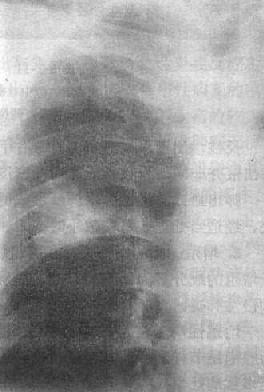

渗出性病变

图3-1-10 渗出性病变

肺浸润肺结核,两肺第1~2前肋间出现边

缘模糊、密度不太高的云絮状影